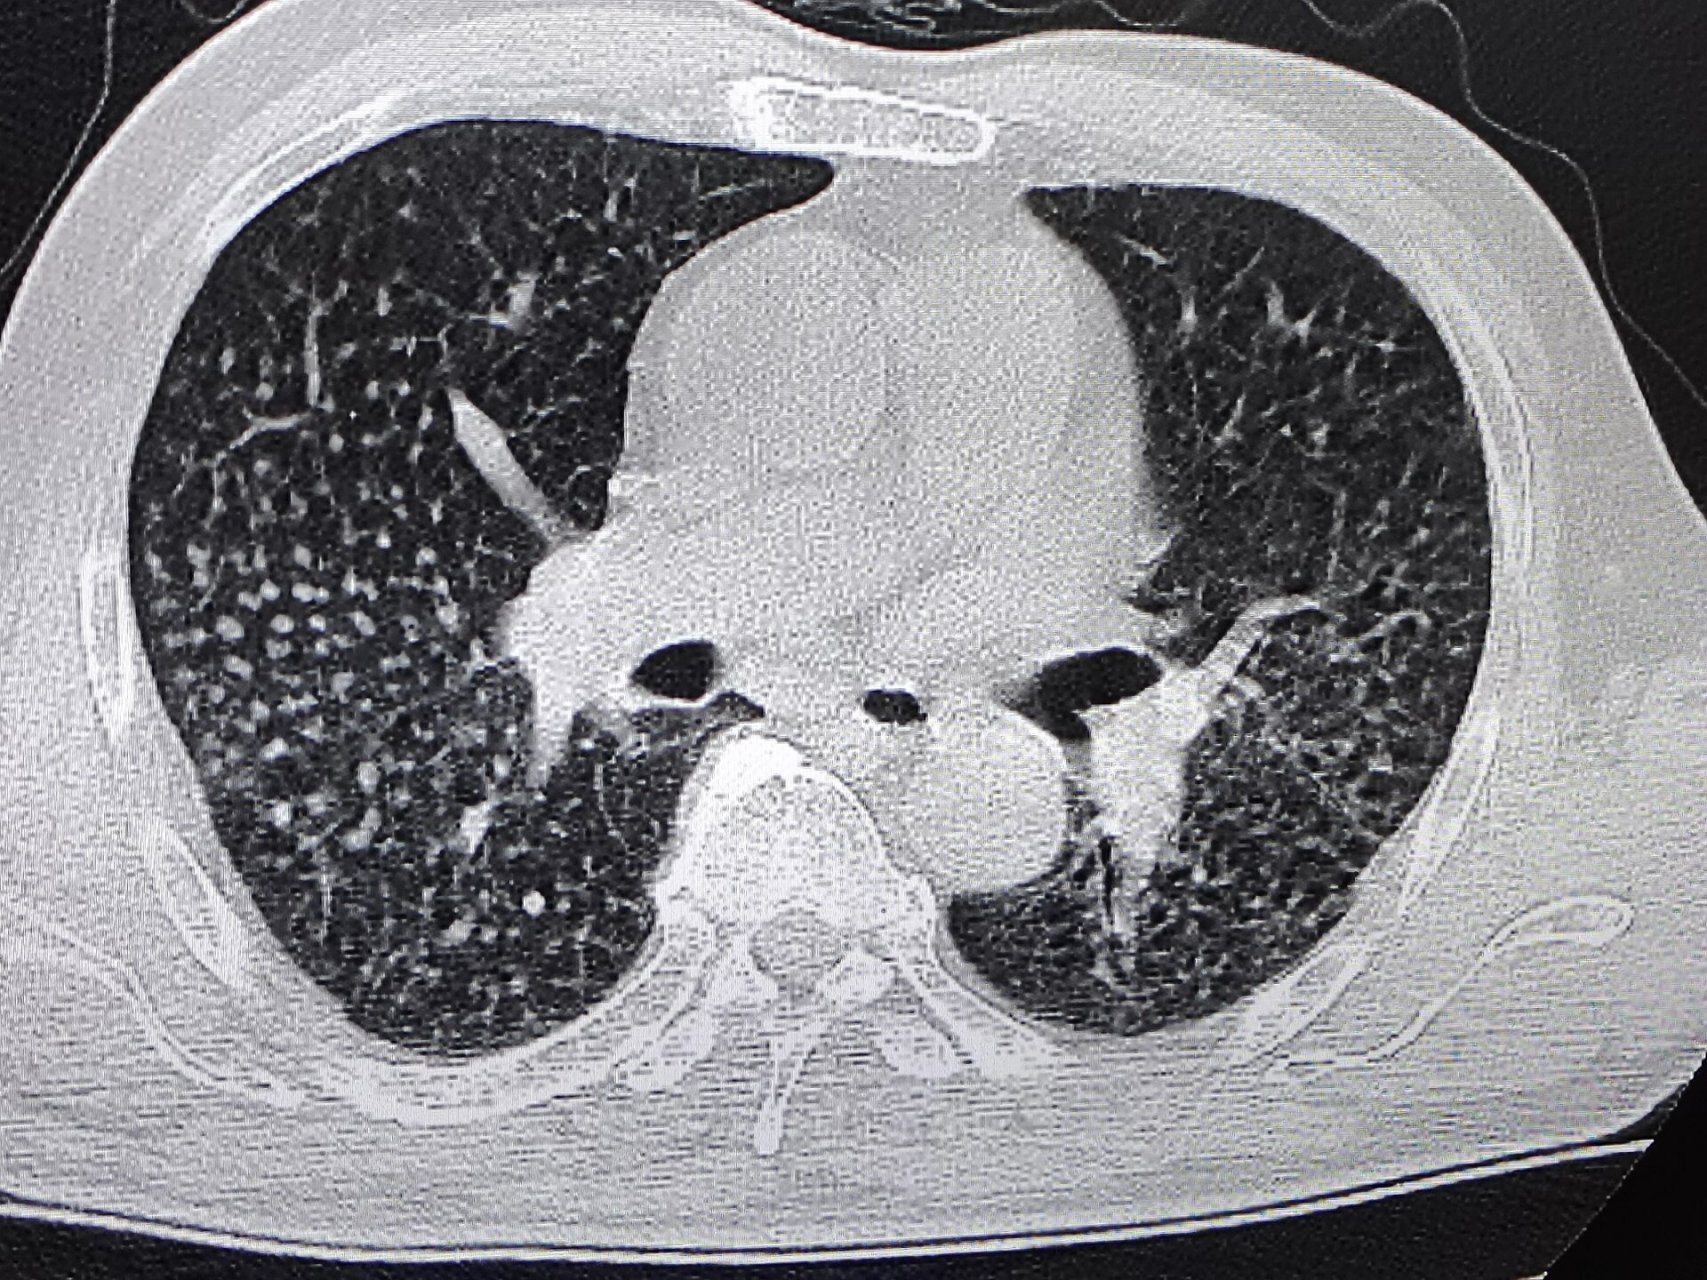

3、矽肺,又称硅肺,是尘肺病中最常见的一种类型该病由长期吸入大量游离二氧化硅粉尘导致,主要特征是肺部广泛的结节性纤维化矽肺在尘肺病中不仅常见,而且是进展最快危害最严重的一种类型洗肺,全称大容量全肺灌洗术,是一种高风险的手术,并非保健手段这种手术对医院的要求极高,因此选择医院至;矽肺病属于尘肺病中较严重的一种,根据肺功能损伤程度分为一 二 三期的,及时发现患病应该尽早脱离粉尘岗位,积极调理治疗是可以控制病情发展的;矽肺是由于在工作过程中大量接触细微的粉尘,进入人体呼吸道后沉积于支气管肺泡内,导致肺组织纤维化所形成的职业病尘肺本身并不会直接导致死亡,有些病人甚至没有明显的自觉症状,但如果合并有肺结核肺炎真菌肺炎慢性阻塞性肺疾病肺心病气胸等并发症时,就有可能导致呼吸衰竭死亡意见建议目前也没有特效抗;通过对肺泡反复灌洗,可以将长期吸入体内的二氧化硅等粉尘灌洗出,从而减轻病情这种方法在一定程度上能够改善患者的症状和生活质量需要注意的是,矽肺病属于职业病,治疗困难,且目前尚无根治方法因此,预防矽肺病的发生至关重要,对于从事相关职业的人群,应做好个人防护,减少粉尘的吸入;矽肺病的治疗需结合脱离污染源控制并发症及增强机体抵抗力,具体方法如下1 脱离粉尘暴露环境确诊矽肺后,首要措施是立即脱离含游离二氧化硅的粉尘作业环境,避免病情进一步加重患者需转移至空气清新无职业暴露风险的场所,减少肺部纤维化的进展风险2 抗感染治疗矽肺患者因肺组织结构破坏,易合并;再生医学的兴起,让人们看到矽肺治疗的曙光以干细胞移植技术为代表的再生医学技术,通过运用干细胞再生人体多种体细胞的生物学特性,来治疗各种临床难治性疾病干细胞是一类尚未分化未发育好能生成各种器官组织的全能细胞,是具有自我更新高度增殖和多向分化潜能的细胞群,即这些细胞可以通过细胞分裂。